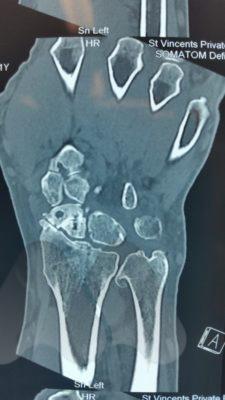

If initial X-Rays do not show the fracture but there is persistent pain and swelling in the radial side of the wrist, your doctor may ask you to have a CT or MRI scan to give more detailed imaging of the area. This can identify occult scaphoid fractures and the amount of displacement or other injured structures in the area such as distal radius fractures, scapholunate ligament injuries, trapezium fractures or other ligamentous injuries. This helps guide you and your doctor’s choice of treatment.

In situations where scaphoid fractures have been initially missed but identified later, before the onset of arthritis, the diagnosis of a scaphoid non-union is made. These situations often require surgery as the chance of healing by late casting is unlikely to result in fracture healing. The surgery aims to clear out the scar tissue at the fracture site and sometimes add fresh bone from either the wrist or hip to add structural support and fill in defects in the bone and insert a screw for fracture fixation to get the bone to heal and restore normal stability to the wrist. The long term aims are to try and slow the progression towards arthritis in the wrist, however, research studies have shown that this can still develop. In some circumstances where the quality of the bone is poor or has lost it’s blood supply, bone graft with it’s own blood supply is taken from the wrist or knee and connected to the scaphoid.